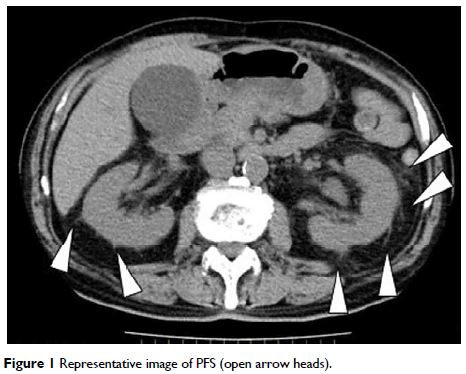

Original Research 简明总结

- 作者:Hirotaka Fukami, Yoichi Takeuchi, Saeko Kagaya, Yoshie Ojima, Ayako Saito, Hiroyuki Sato, Ken Matsuda, Tasuku Nagasawa

- 期刊:International Journal of General Medicine